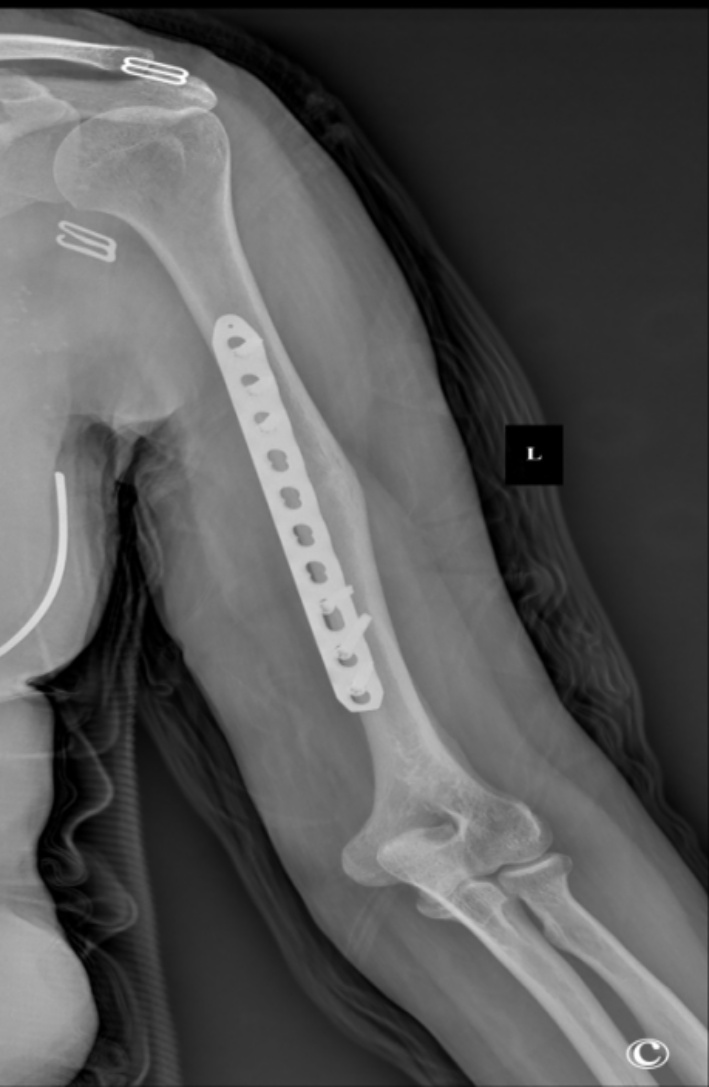

患者术后恢复顺利,无桡神经麻痹、切口感染、血管损伤等并发症。术后1天复查X线片示骨折解剖复位,内固定位置良好(图2)。术后第2天开始进行肩、肘关节被动功能锻炼,逐步过渡至主动活动。术后6个月随访X线片显示骨折线模糊,骨痂形成良好,内固定无松动、断裂(图3)。术后16个月返院拆除内固定装置,X线片示骨折愈合牢固,无畸形(图4)。拆除内固定前,手术切口愈合良好,瘢痕隐蔽,患者对外观满意(图5)。截至末次随访,患者肩关节平均主动前屈达165˚ ± 10˚,外展155˚ ± 12˚,内旋达到T8椎体水平;肘关节平均主动活动范围(屈–伸)为125˚ ± 15˚(屈曲140˚ ± 5˚,伸直15˚ ± 10˚),前臂平均旋前80˚ ± 5˚,旋后85˚ ± 5˚。采用标准化量表评估,患者平均DASH上肢功能障碍评分为12分 ± 5分,表明仅有轻度功能障碍;平均MEPS肘关节功能评分为92分 ± 6分,对应“优秀”等级。疼痛控制方面,术后平均静息态VAS疼痛评分为1.5分 ± 1.0分,活动时为2.5分 ± 1.5分,已恢复正常工作和生活。

Figure 3. A 6-month postoperative radiograph confirms that the plate is in situ, with the fracture line becoming obscured

3. 术后6个月X片示钢板固定在位,骨折线模糊